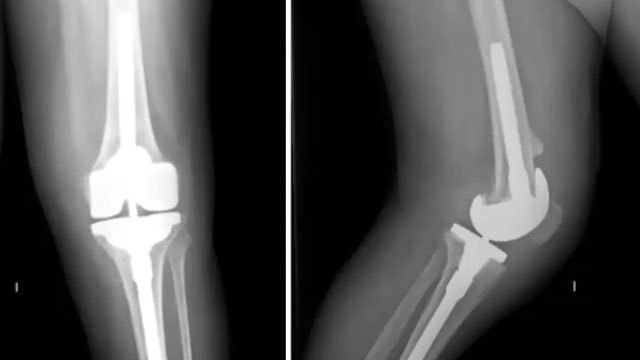

The Revision Knee Replacement Surgery Procedure

The revision procedure is typically more complex than a primary knee replacement and may involve the following steps:

- Preoperative Assessment: A comprehensive evaluation, including imaging studies, is conducted to assess the condition of the existing implant and surrounding structures.

- Surgical Approach: A new incision is made, often using the previous surgical site, to access the knee joint.

- Implant Removal: The existing implant is carefully removed, taking care to preserve as much surrounding bone and tissue as possible.

- Addressing Complications: If present, any infection or bone loss is treated, which may involve using bone grafts or additional stabilising measures.

- Implant Placement: A new prosthesis is then implanted, tailored to the patient’s specific anatomy and needs, ensuring optimal alignment and stability.

- Closure: The incision is closed with sutures or staples, and a sterile dressing is applied.

The surgery typically lasts between two to four hours, depending on the complexity of the case.